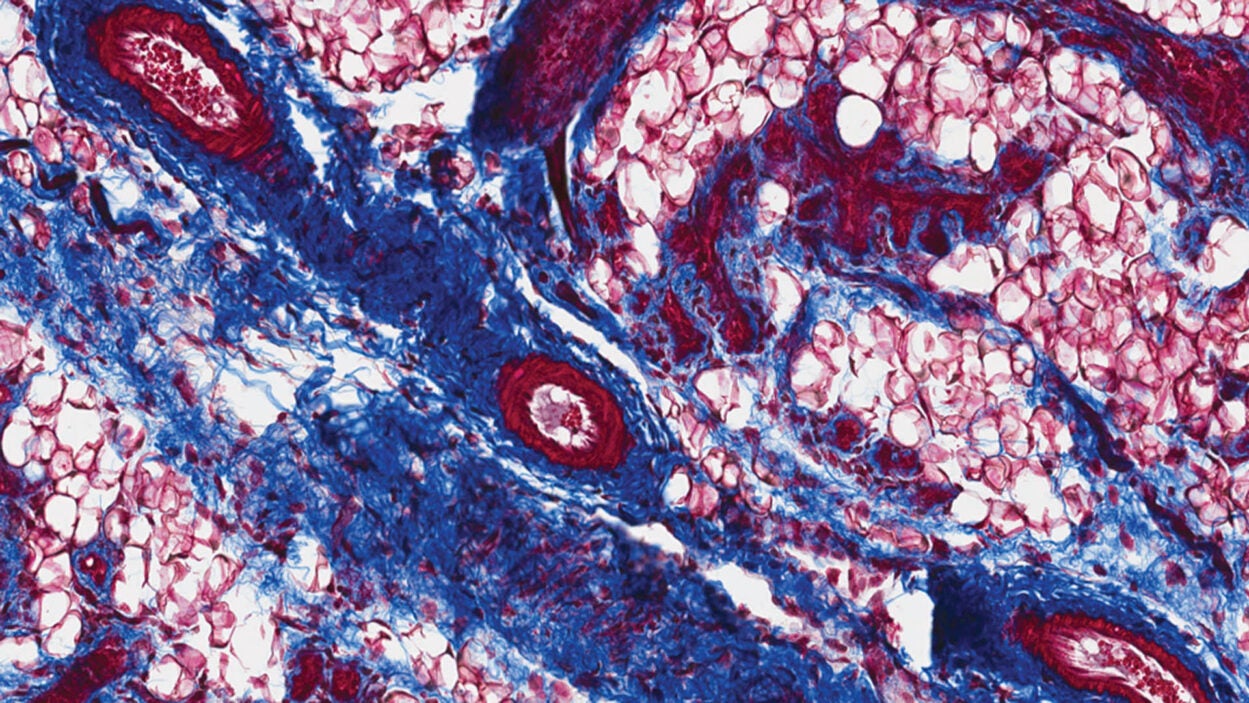

Feature

An angry peacock is no joke. Like the colorful bird and its tall tail feathers, cancer biology can make for some eye-catching images. Read the story »

That’s not the Starship Enterprise burning up in space. It’s an up-close look at precancerous pancreatic lesions and the mucus they produce. Read the story »